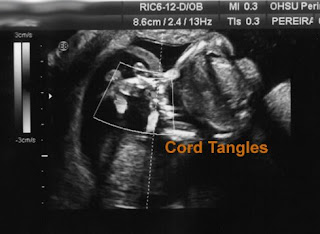

Baby B's heart rate had been having decels. The rate at which they were deceling was increasing and his heart started dipping into the 'not so good' zone. The team of doctors had come in and told me that I was going to be put onto 24 hour monitoring so they could see if a decel pattern was forming. I admit I was scared and I kept thinking, I know I told the nurses the other day that I was so uncomfortable and ready to be done.. BUT I really wasn't! (Especially now that they told me things were getting iffy.) I had made it to that 30+ wk milestone, and everyone kept assuring me that if the boys needed to be taken they would have a great chance. So scared, sitting in that little hobbit hole of a hospital room alone and praying that everything would be all right. I think I had squeezed my cross pendant so hard and for so long that it was embedded into my hand!